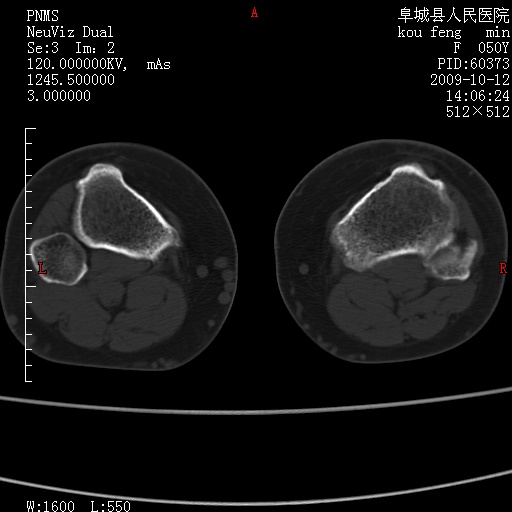

女性,50岁。【请提供患者临床症状体征】

右膝关节退行性改变,关节游离鼠。

右膝关节退行性改变,滑膜黏液囊钙/骨化并游离。